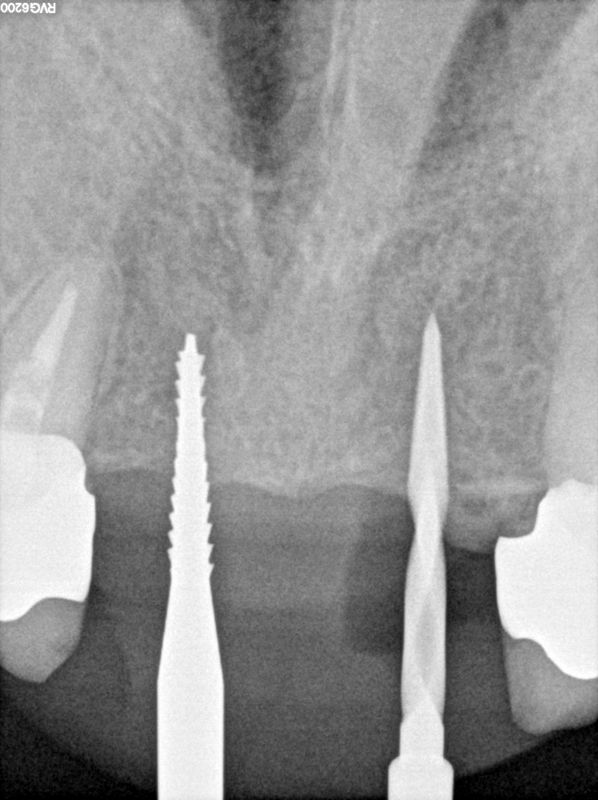

fredlibc | all galleries >> Galleries >> NSankhyan - immediate 13, impls 1121 and 25 with grafting > 11,21.jpg

11,21.jpg